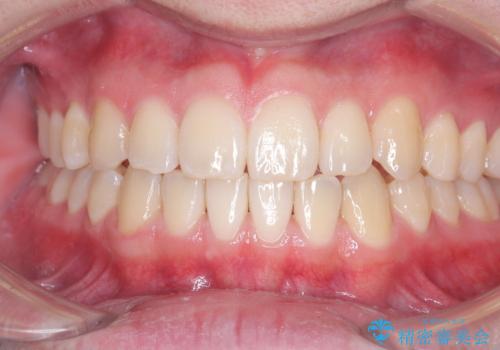

- 八重歯が気になるとのことでご来院されました。お口の中を確認すると、上の前歯がスペース不足で押し出され、少し前に出ている状態でした。抜歯せずに整えるため、奥歯を少しずつ後ろに動かしながら(遠心移動)、歯と歯の間をわずかに削るIPRを行ってスペースを作ることにしました。また、上下の噛み合わせを整えるために2級ゴム(エラスティック)を使用する方針を立てました。

マウスピースを段階的に交換しながら、奥歯を少しずつ後ろへ動かし、八重歯がきれいに並ぶよう調整しました。前歯の突出感を抑えるためにIPRを行い、スムーズに配列。さらに、2級ゴムを活用して噛み合わせも改善しました。治療後は、自然な歯並びになり、笑顔に自信が持てるようになったと喜んでいただきました。